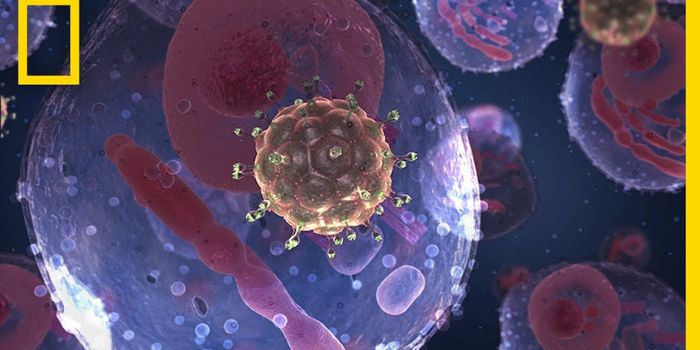

SEP 20, 2021Genetics & GenomicsHuman immunodeficiency virus (HIV) is a retrovirus, which is a type of virus that can write its genetic material into th ...